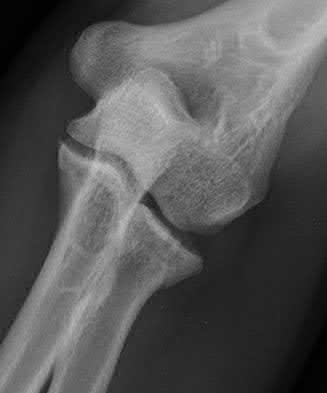

2. # A 35-year-old woman is involved in a head-on collision while driving. Initial radiographs are shown in Figures 8a and 8b. Injury to what vessel increases the risk for osteonecrosis of the injured bone?

5. Artery of the tarsal sinus Corrent answer: 4

The patient has a Hawkins type III talar neck fracture-dislocation with a risk of osteonecrosis ranging from 69% to 100%. Anatomic studies have shown that the artery of the tarsal canal supplies the lateral two thirds of the talar body.

The other vessels listed provide no significant contribution to the talus.